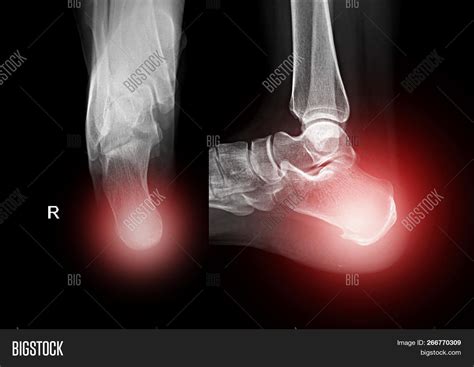

• Severe pain in the heel area

• Swelling and bruising

• Difficulty walking or bearing weight on the affected foot

• Visible deformity or misalignment of the heel

These symptoms can indicate a fracture or other serious condition that requires immediate medical attention. A Calcaneus X Ray helps to confirm the diagnosis and guide the appropriate treatment plan.